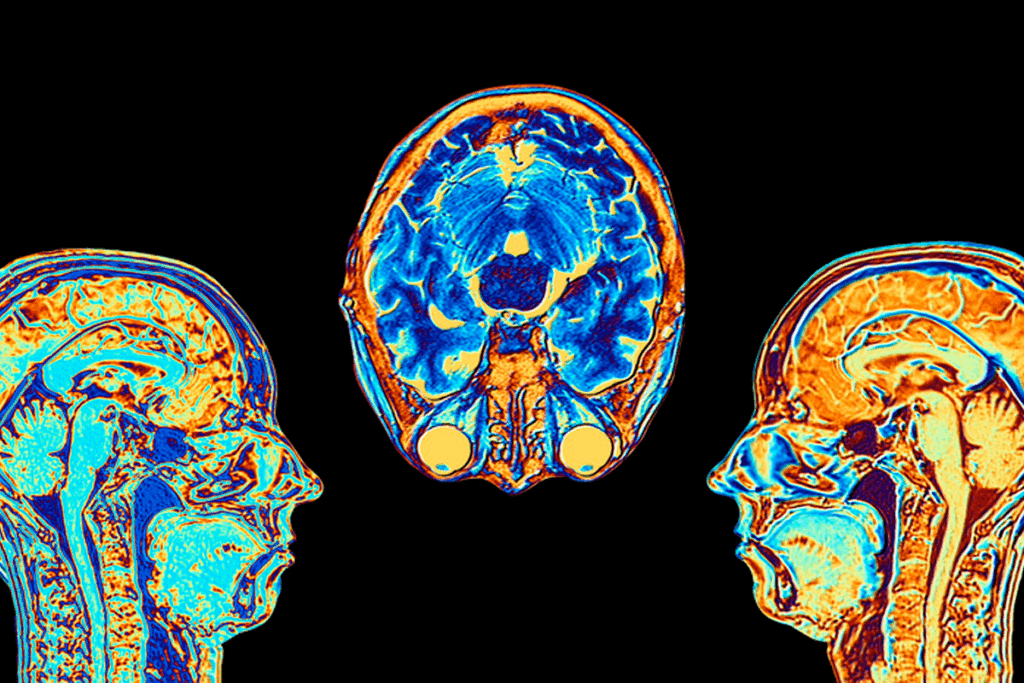

Before starting, patients go through many steps to ensure safety and success. This includes a full medical check-up, imaging tests like angiography or MRI, and talks with our neurovascular experts. They discuss the procedure’s risks and benefits.

- Imaging studies (e.g., angiography, MRI)